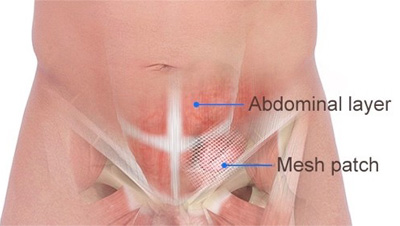

Overview

Package includes:

Days in hospital : 3 to 4 Days (For patient and one attendant)

Days in hotel : 15 Days (For patient and one attendant)

Room type in hospital : Shared

Room type in hotel : Private

Hotel category: Standard

Value added benefits of the Hernioplasty Inguinal with Mesh:

Ø Doctor consultation charges

Ø Lab tests and diagnostic charges

Ø Room charges inside hospital during the procedure

Ø Surgeon Fee

Ø Nursing charges

Ø Hospital surgery suite charges

Ø Anesthesia charges

Ø Routine medicines and routine consumables (bandages, dressings etc.)

Ø Food and Beverages inside hospital stay for patient and one attendant.

Extra benefits:

ü Interpreter

ü Visa assistance

Ø Site tourism of the city

Ø Follow up with the doctor

Ø Airport pick up and drop

Ø Free online consultation with the doctor

Ø Priority appointments with the doctor

Ø Room upgrade from sharing to private

Overview

Package includes:

Days in hospital : 2 to 3 Days (For patient and one attendant)

Days in hotel : 15 Days (For patient and one attendant)

Room type in hospital : Shared

Room type in hotel : Private

Hotel category: Standard

Value added benefits of the Hernioplasty Inguinal Bilateral with mesh:

Ø Doctor consultation charges

Ø Lab tests and diagnostic charges

Ø Room charges inside hospital during the procedure

Ø Surgeon Fee

Ø Nursing charges

Ø Hospital surgery suite charges

Ø Anesthesia charges

Ø Routine medicines and routine consumables (bandages, dressings etc.)

Ø Food and Beverages inside hospital stay for patient and one attendant.

Extra benefits:

ü Interpreter

ü Visa assistance

Ø Site tourism of the city

Ø Follow up with the doctor

Ø Airport pick up and drop

Ø Free online consultation with the doctor

Ø Priority appointments with the doctor

Ø Room upgrade from sharing to private